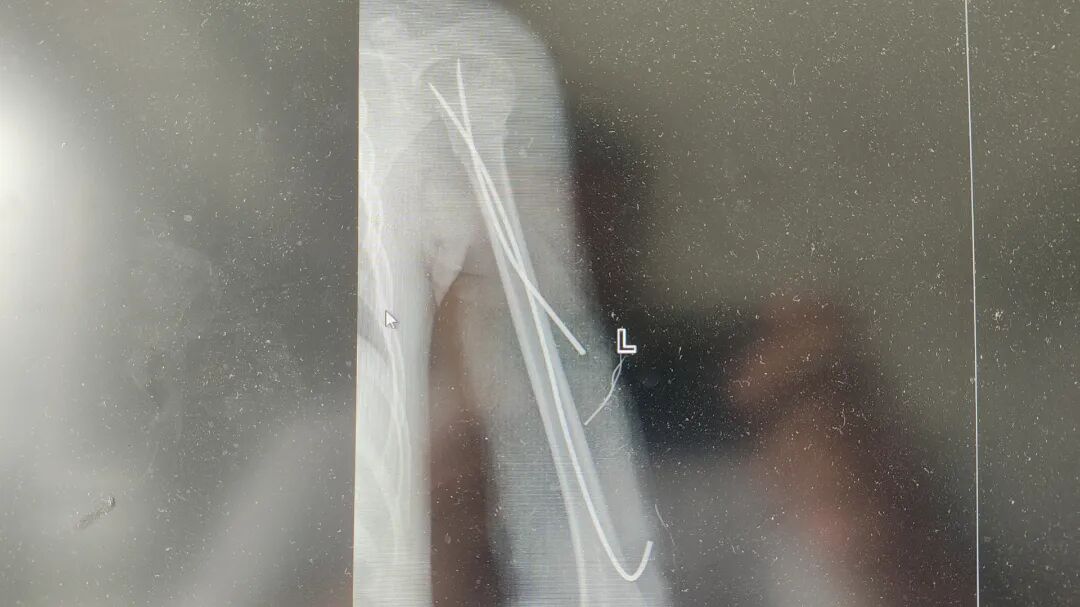

◆ ◆ ◆ ◆ 小辉(化名)今年7岁,在家玩耍时不慎从沙发上摔下,伤后即感左上臂出现剧烈疼痛及肿胀伴有活动障碍。遂即来我院急诊科就诊,门诊医师行拍片示“左肱骨近段骨折”,门诊经结合外伤史、症状体征及相关影像学检查后拟以“左肱骨骨折”为诊断,收住骨科继续治疗。 (入院影像结果) 入院后,骨科主任尹绍猛立即组织团队进行病例讨论,考虑到小辉年龄较小,保守治疗效果欠佳且孩子遵从能力差,有骨折不愈合、畸形愈合等多种可能性,将会导致小辉以后生活有患肢短缩或畸形等情况,经骨科团队讨论后决定为小辉实施左肱骨近段骨折闭合复位+弹性髓内针内固定术。 术中,仅在小辉患肢开个约1cm的小口,对称插入两根弹性髓内针,利用钛合金或不锈钢良好的弹性恢复力作用于骨折,通过髓腔的3个接触点转换成推力和压力,从而使骨折复位。手术非常顺利,仅仅用了30分钟就完成了手术,术后小辉恢复良好,复查骨折断端对位对线良好,畸形纠正。 (术后影像结果) 尹绍猛主任介绍,弹性髓内针适应症广泛,多应用于3至13岁儿童长骨骨折。肥胖者降低年龄标准,消瘦者可适当提高年龄标准,但不宜超过15岁,其中5至10岁非肥胖者最佳,各类长骨新鲜单纯性骨折及干骺端闭合骨折,以横断和短斜形骨折最佳。此外还可应用在有足够骨皮质支撑的长斜形或螺旋形骨折。弹性髓内针技术属于微创闭合穿针内固定,骨折处没有切口,具有创伤小、操作简单、骨折复位满意、固定简便可靠,骨折愈合快,并发症少,住院时间短等特点。该技术已得到世界范围内小儿骨科医生的广泛推崇,成为治疗儿童长骨骨折的首选方法。 弹性髓内针技术的特点 1.创伤小、留疤小、伤口美观; 2.愈合快,住院时间短,不影响生活学习,骨折愈合后取出内固定简单,仅需切开皮下拔出即可,节省了时间和费用; 3.疗效好,骨折复位满意,固定简便可靠,对断端血供影响小,有利于骨痴生长。 4. 应用广,可应用于3至13岁儿童长骨骨折,其中5至10岁非肥胖者最佳。